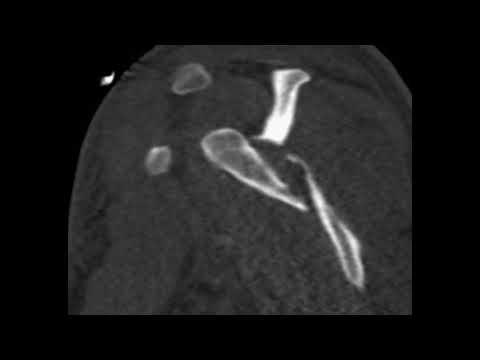

247 Hz : Scapula (RIFE Healing Frequency)